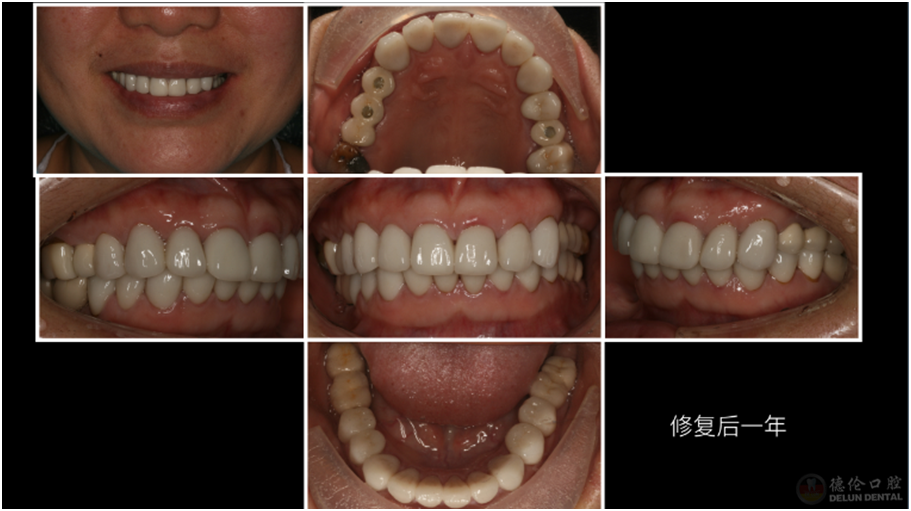

患者症状:牙齿龋坏、四环素牙、牙齿缺失。

治疗方法:治疗牙髓炎和根尖周炎的患牙、拔除残根残冠、升高咬合,种植修复及全冠修复。

术后: